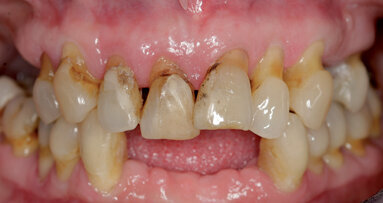

Pro účely statistické analýzy byly použity univariační regresní modely ve vztahu jak k implantátům tak pacientům. Celkem bylo zkontrolováno 460 krátkých implantátů, v délkách od 4 do 9 mm, použitých u 199 pacientů a sledovaných až po dobu devíti let. Míra zachování krátkých implantátů byla 95,86 procenta a 92,96 procenta a úspěšnost 90,00 procenta a 83,41 procenta, hodnoceno vzhledem k počtu implantátů a zúčastněných pacientů. Periimplantitida byla hlášena jako příčina selhání krátkého zubního implantátu v 73,91 % případů. Univariační regresní modely odhalily nižší úspěšnost při implantaci u ženského pohlaví. Kromě toho bylo zjištěno, že kouření a periodontitida v anamnéze mají významný negativní vliv na přijetí krátkých implantátů, posuzováno ve vztahu k implantátům i pacientům.

Tyto výsledky podporují použití krátkých implantátů jako předvídatelné možnosti dlouhodobé léčby. Kouření a periodontitida v anamnéze jsou však považovány za potenciální rizikové faktory pro úspěšnost krátkých implantátů. Podle vědců jsou tyto výsledky v souladu se závěry jiných dlouhodobých studií.